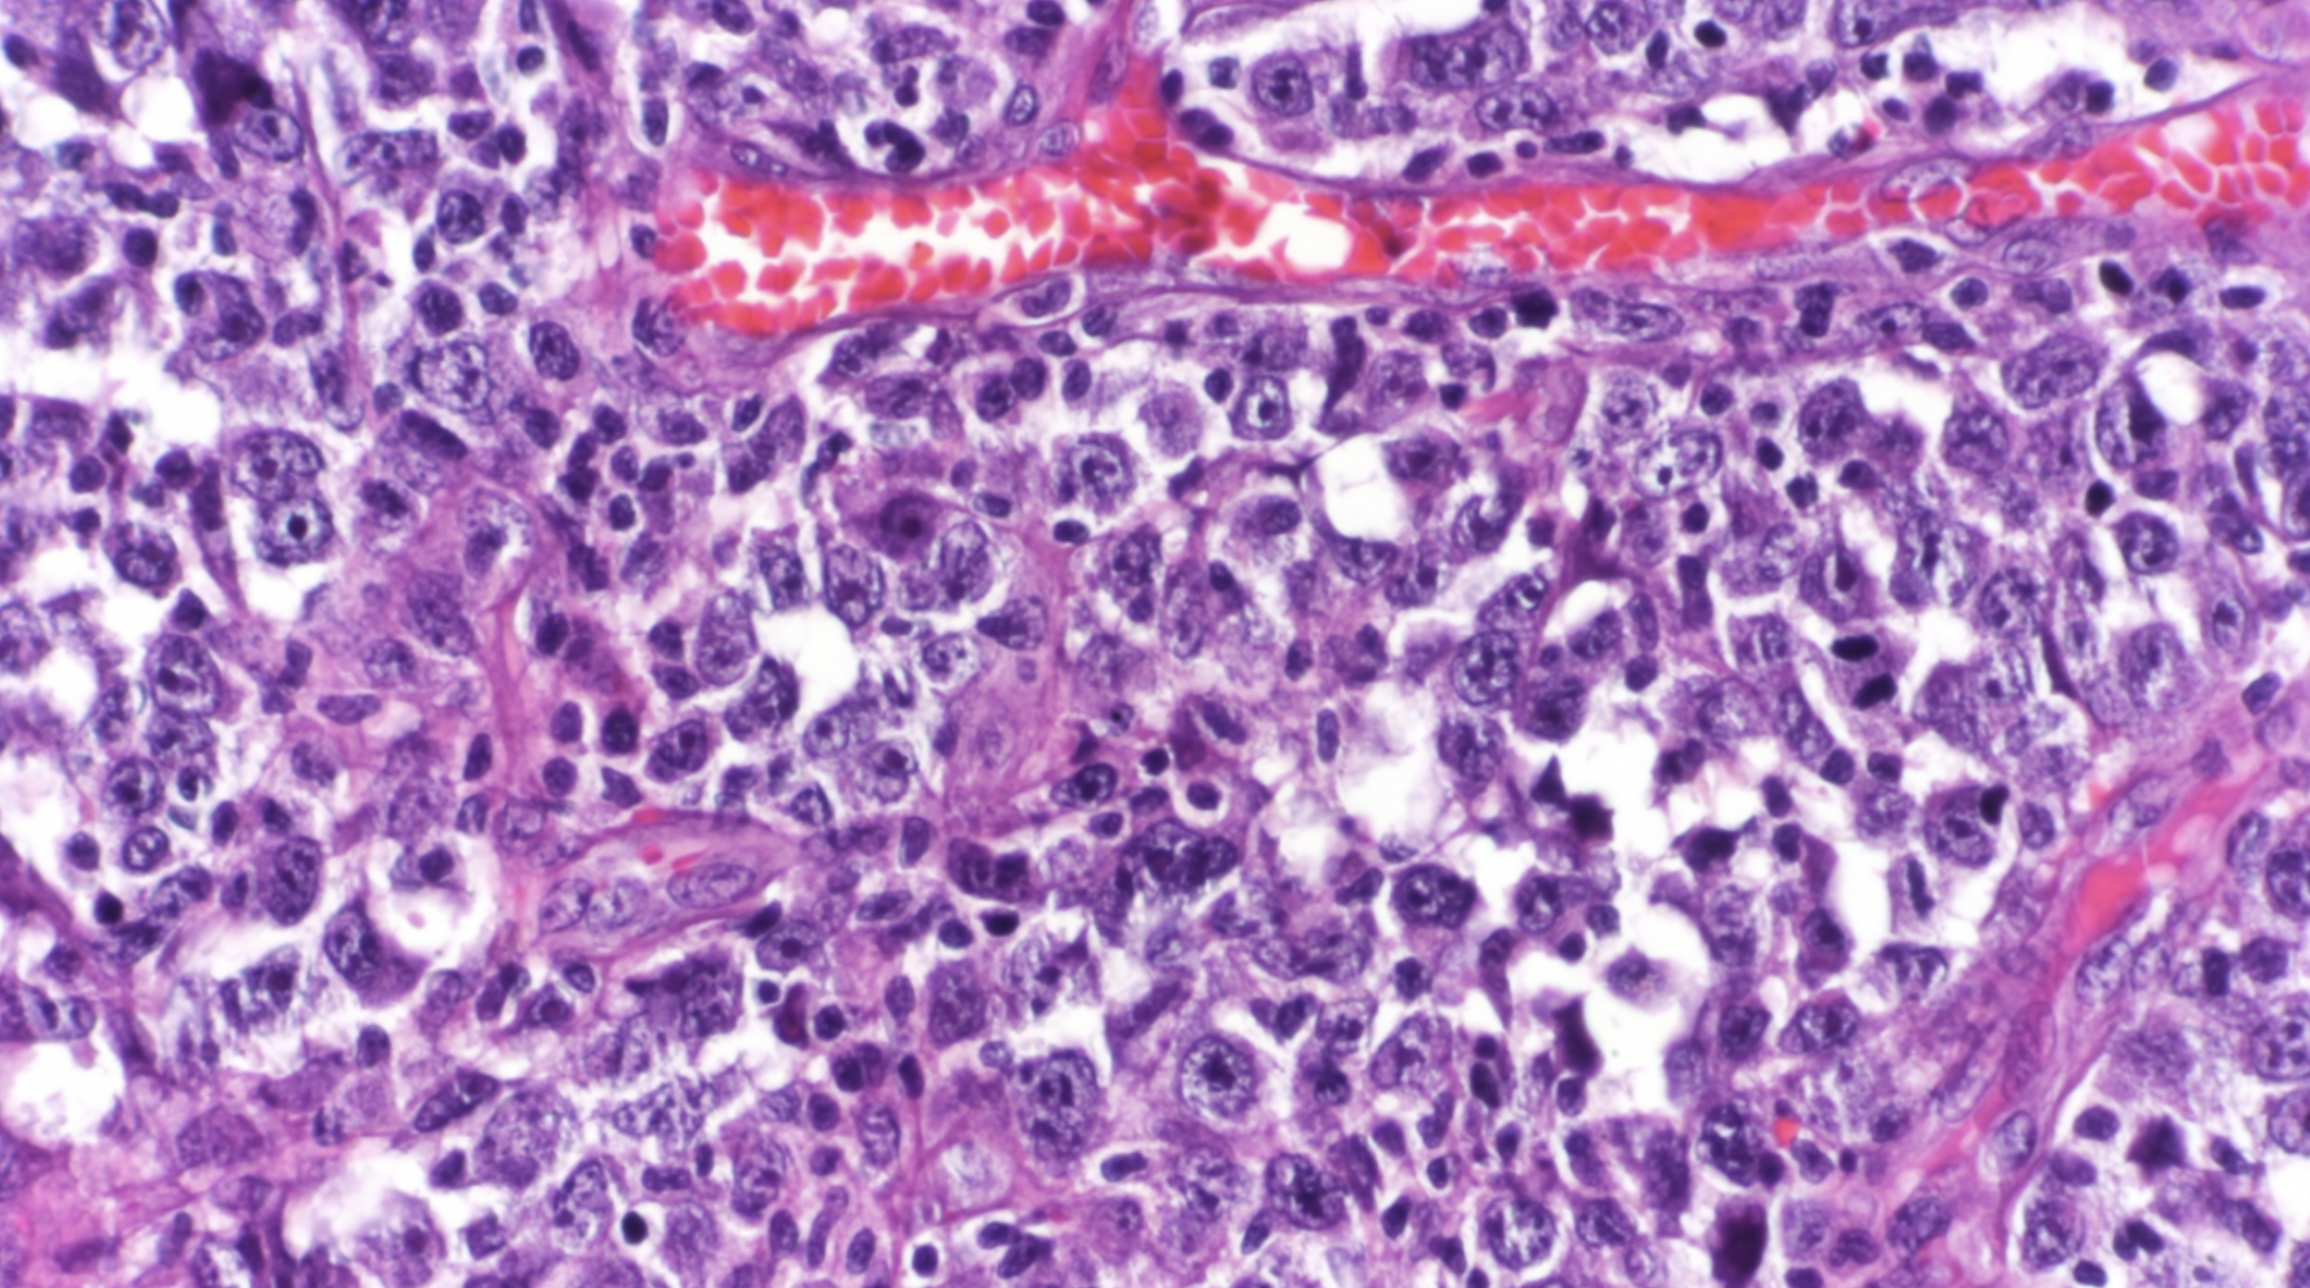

The environment surrounding the cancerous cells of a lymphoma tumor has a strong influence on the progression of these blood-cell cancers and their responses to therapies, according to a study by Weill Cornell Medicine investigators. Measuring this molecular and cellular environment, or “microenvironment,” may represent a new type of precision-medicine approach to lymphoma classification and treatment.

The researchers, who report their findings Feb. 4 in Cancer Discovery, a journal of the American Association for Cancer Research, analyzed the patterns of gene activity in tumor samples taken from the lymph nodes of thousands of lymphoma patients. They found that the cells within these tumors, which include both cancer cells and healthy cells, produce molecules that collectively constitute a distinct microenvironment for the tumors, influencing their biology and growth. The scientists also found that lymphoma microenvironments tend to occur in one of four broad categories, which range from tumor growth-restricting to tumor-growth enhancing. The researchers demonstrated in an animal model that by experimentally modifying the lymphoma microenvironment they could slow the cancer’s growth.

In the study, the researchers, using BostonGene’s solution, analyzed data on gene activity detected in samples taken from more than 4,600 DLBCL patients. Focusing on microenvironment-sustaining patterns of gene activity within lymphoma and tumor-resident non-lymphoma cells, they discovered that the inferred microenvironments tended to fall into four broad categories.

These microenvironment categories were generally associated with different ecosystems of cells and treatment responsiveness, from ecosystems that are similar to healthy lymph nodes and more responsive to degraded, depleted ecosystems and less responsive, and appeared to represent a new and independently useful classification of lymphomas.